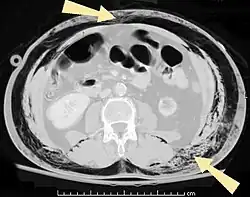

![]() Una tomografía computarizada abdominal de un paciente con enfisema subcutáneo (flechas) | ||

Diversos casos son fácilmente diagnosticados por los signos característicos de la condición.[1] En otros se dificulta el diagnóstico debido a que los signos son imperceptibles.[12] Se utiliza la imagen médica para diagnosticar o confirmar la condición. En radiografías torácicas, el enfisema se observa como estriaciones radiolucentes en el área del músculo pectoral mayor. El aire en los tejidos subcutáneos puede interferir con la radiografía torácica, por lo tanto puede esconder condiciones graves como el neumotórax.[16] También puede reducir la efectividad del ultrasonido torácico.[24] Por otr lado, dado que el enfisema es visible en los rayos X torácicos antes que el neumotórax, su presencia puede utilizarse para inferir esta última lesión. Esta condición también se observa en las tomografías computarizadas como zonas oscuras. Normalmente, al ser una técnica muy sensible, es posible encontrar el lugar exacto desde donde el aire ingresa a los tejidos blandos.[12]